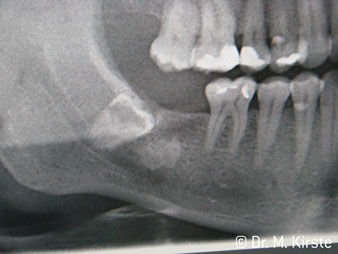

Elegir el ángulo de 45º ofrece múltiples ventajas de uso. Los odontólogos dedicados a cirugía (para quienes se desarrolló principalmente esta pieza de mano) se percatarán de inmediato de que se puede trabajar de forma muy específica. En especial en la remoción de las muelas del juicio (Fig. 2), no es necesaria una gran abducción de las partes blandas en la zona del carrillo (Fig. 3). El diseño del cabezal de la pieza de mano, combinado con los suaves giros del cabezal durante la preparación, permite trabajar de forma rápida y segura en la zona retromolar.

El nuevo diseño de los rodamientos dentro del cabezal de la pieza de mano garantiza el funcionamiento silencioso de la fresa, en la separación del diente o la raíz (Fig. 4-9) se muestra una impresionante imagen de corte sin efectos de impacto.